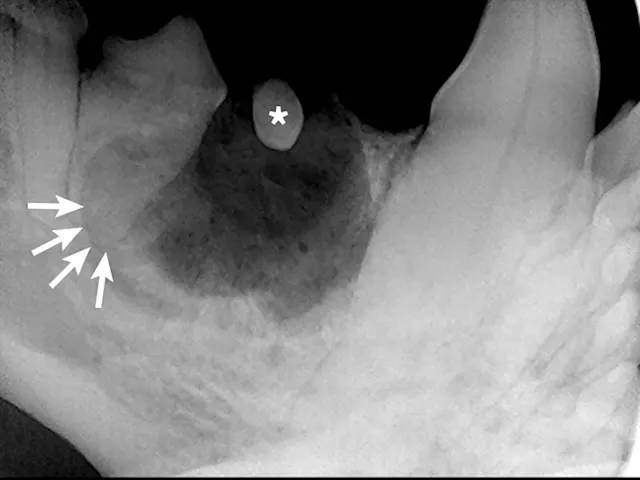

Full-mouth radiographs were obtained, with particular attention on the clinically missing mandibular premolars and the areas affected by gingival masses. Radiographs revealed unerupted mandibular 1st premolars situated in apparent cystic lesions, expansion of which resulted in involvement of the mandibular canines and 2nd premolar teeth. The apical portion of the mesial root of the mandibular premolar (306) was partially resorbed. Maxillary premolars were rotated bilaterally, but there were no periodontal consequences. Incidental findings included a supernumerary maxillary left first premolar 1 (205) and fusion of the roots of the left and right mandibular premolar 2 teeth (306 and 406). Horizontal alveolar bone loss was present at the area of 206, with radiolucency of the furcation area of 206 (Figures 3-6); the buccal aspect of 206 was covered by the gingival mass. Probing of the furcation was possible only from the palatal side and did not reveal furcation involvement.